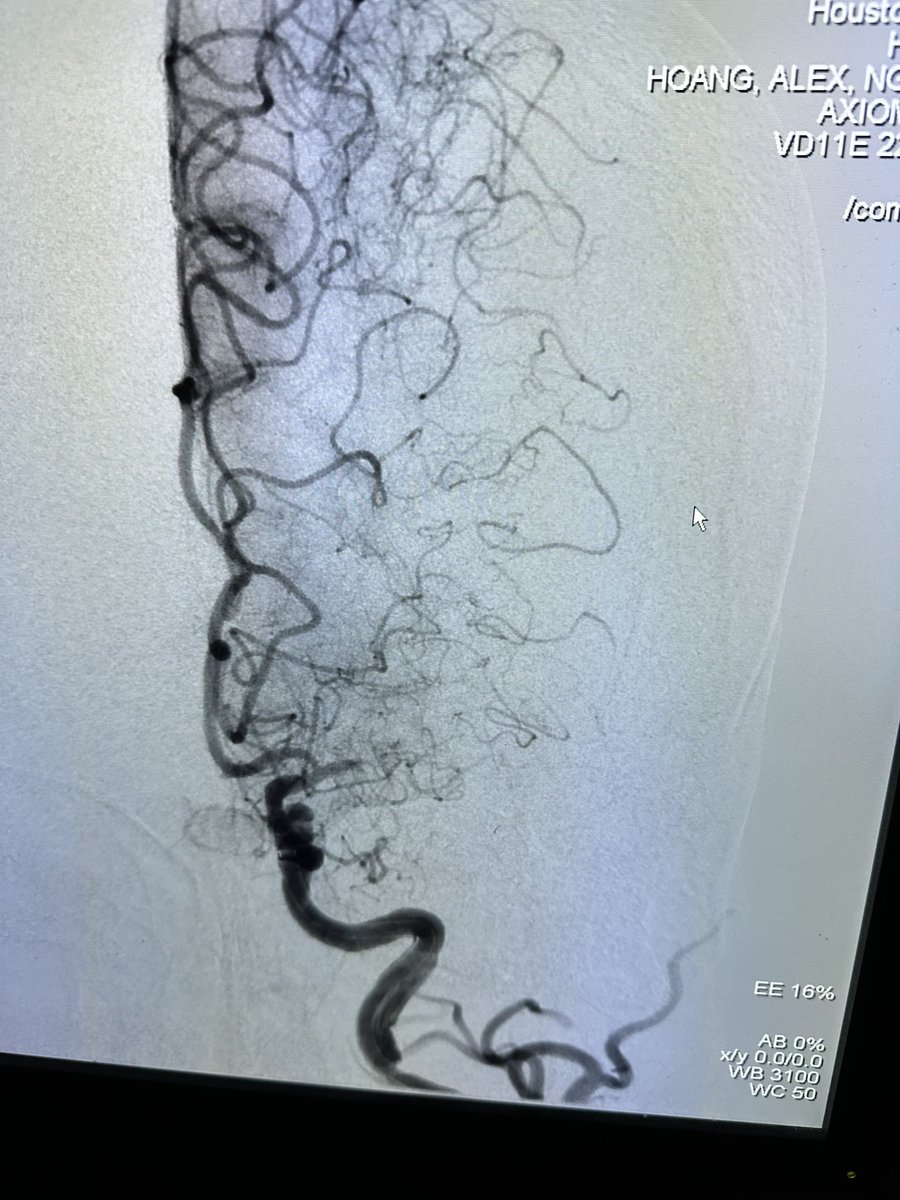

Great talk by @ShahidNimjee about VWF inhibiting aptamer for thrombolysis. This research has come along way and will improve stroke therapy in the future. It may be the beginning of the end of stroke mechanical thrombectomy. #SNIS2023 @OSUWexMed @NeurosurgeryOSU